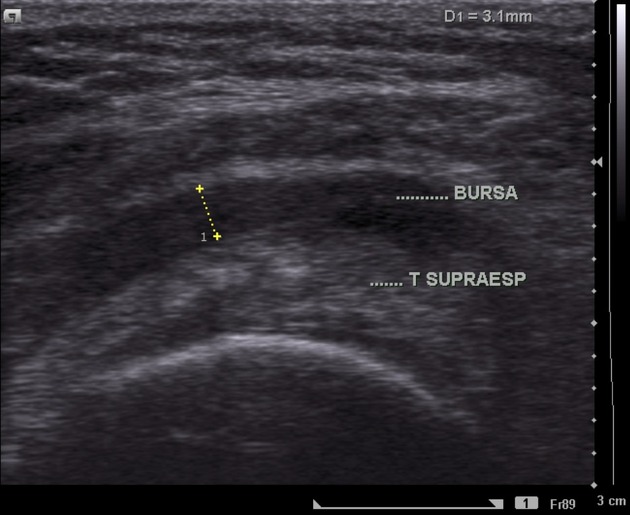

En caso de patología, la imagen se vería de la siguiente forma:

Es común que la bursitis coexista con una tendinopatía del supraespinoso.